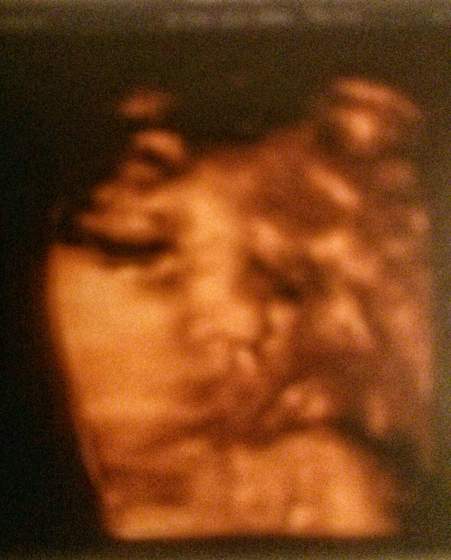

Na usg wszystko OK. Mała waży 3288 g plus/minus 500 g. Tętno OK. Lekarz powiedział że mała jest taka fajna - dokładnie wychodzą wymiary z usg jak z ostatniej miesiączki. Nie jest za duża, a tego się bałam, bo przy cukrzycy podobno łatwo jest dzidziusia "utuczyć".